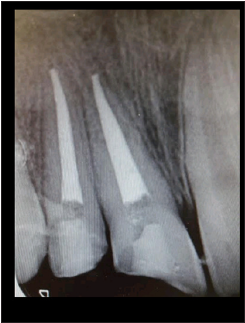

Three days later, the patient had returned with a complaint of

spontaneous pain. A root canal was performed in tooth no.12 and

a root canal retreatment was performed in tooth no.11. (Figure 2).

The teeth crowns were sealed using glass ionomer (GC Fuji II®, GC

Corporation, Tokyo, Japan).

Figure 2: A periapical x-ray after a root canal was performed in tooth no.12 and a root canal retreatment was performed in tooth no.11.